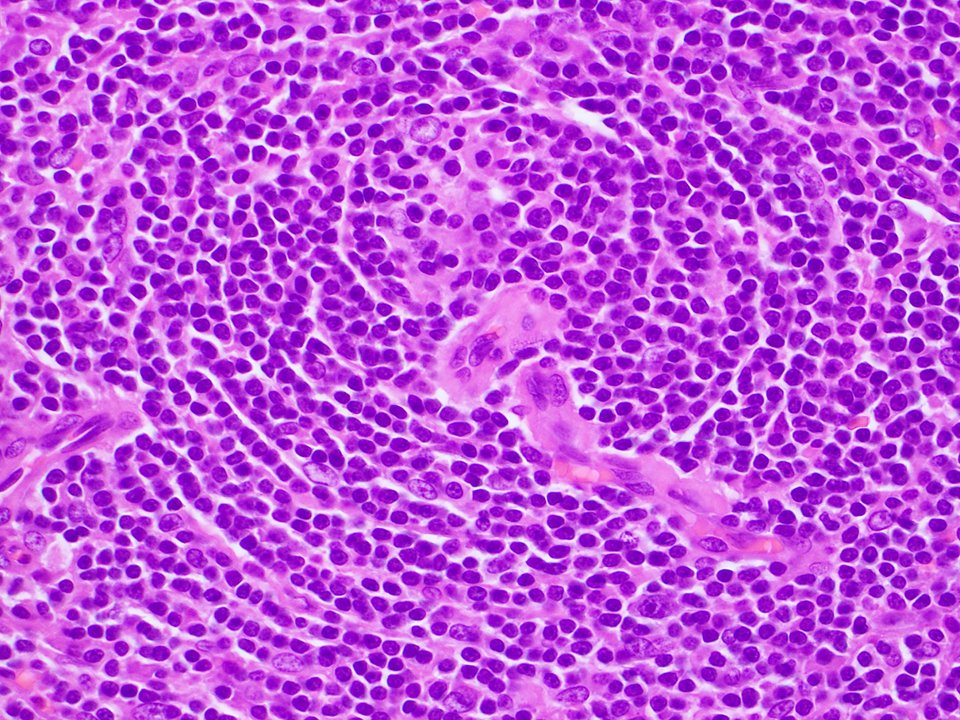

70ish y/o male, gastric lesion, excision. Tumor is locaded in the submucosa, with infiltrative growth to the subserosal layer. Cells are arranged in solid sheets. Monomorphic appearance. Let's have a closer look! Follow the thread... 🧵

DrJuhlin's tweet image. 70ish y/o male, gastric lesion, excision. Tumor is locaded in the submucosa, with infiltrative growth to the subserosal layer. Cells are arranged in solid sheets. Monomorphic appearance. Let&apos;s have a closer look! Follow the thread... 🧵